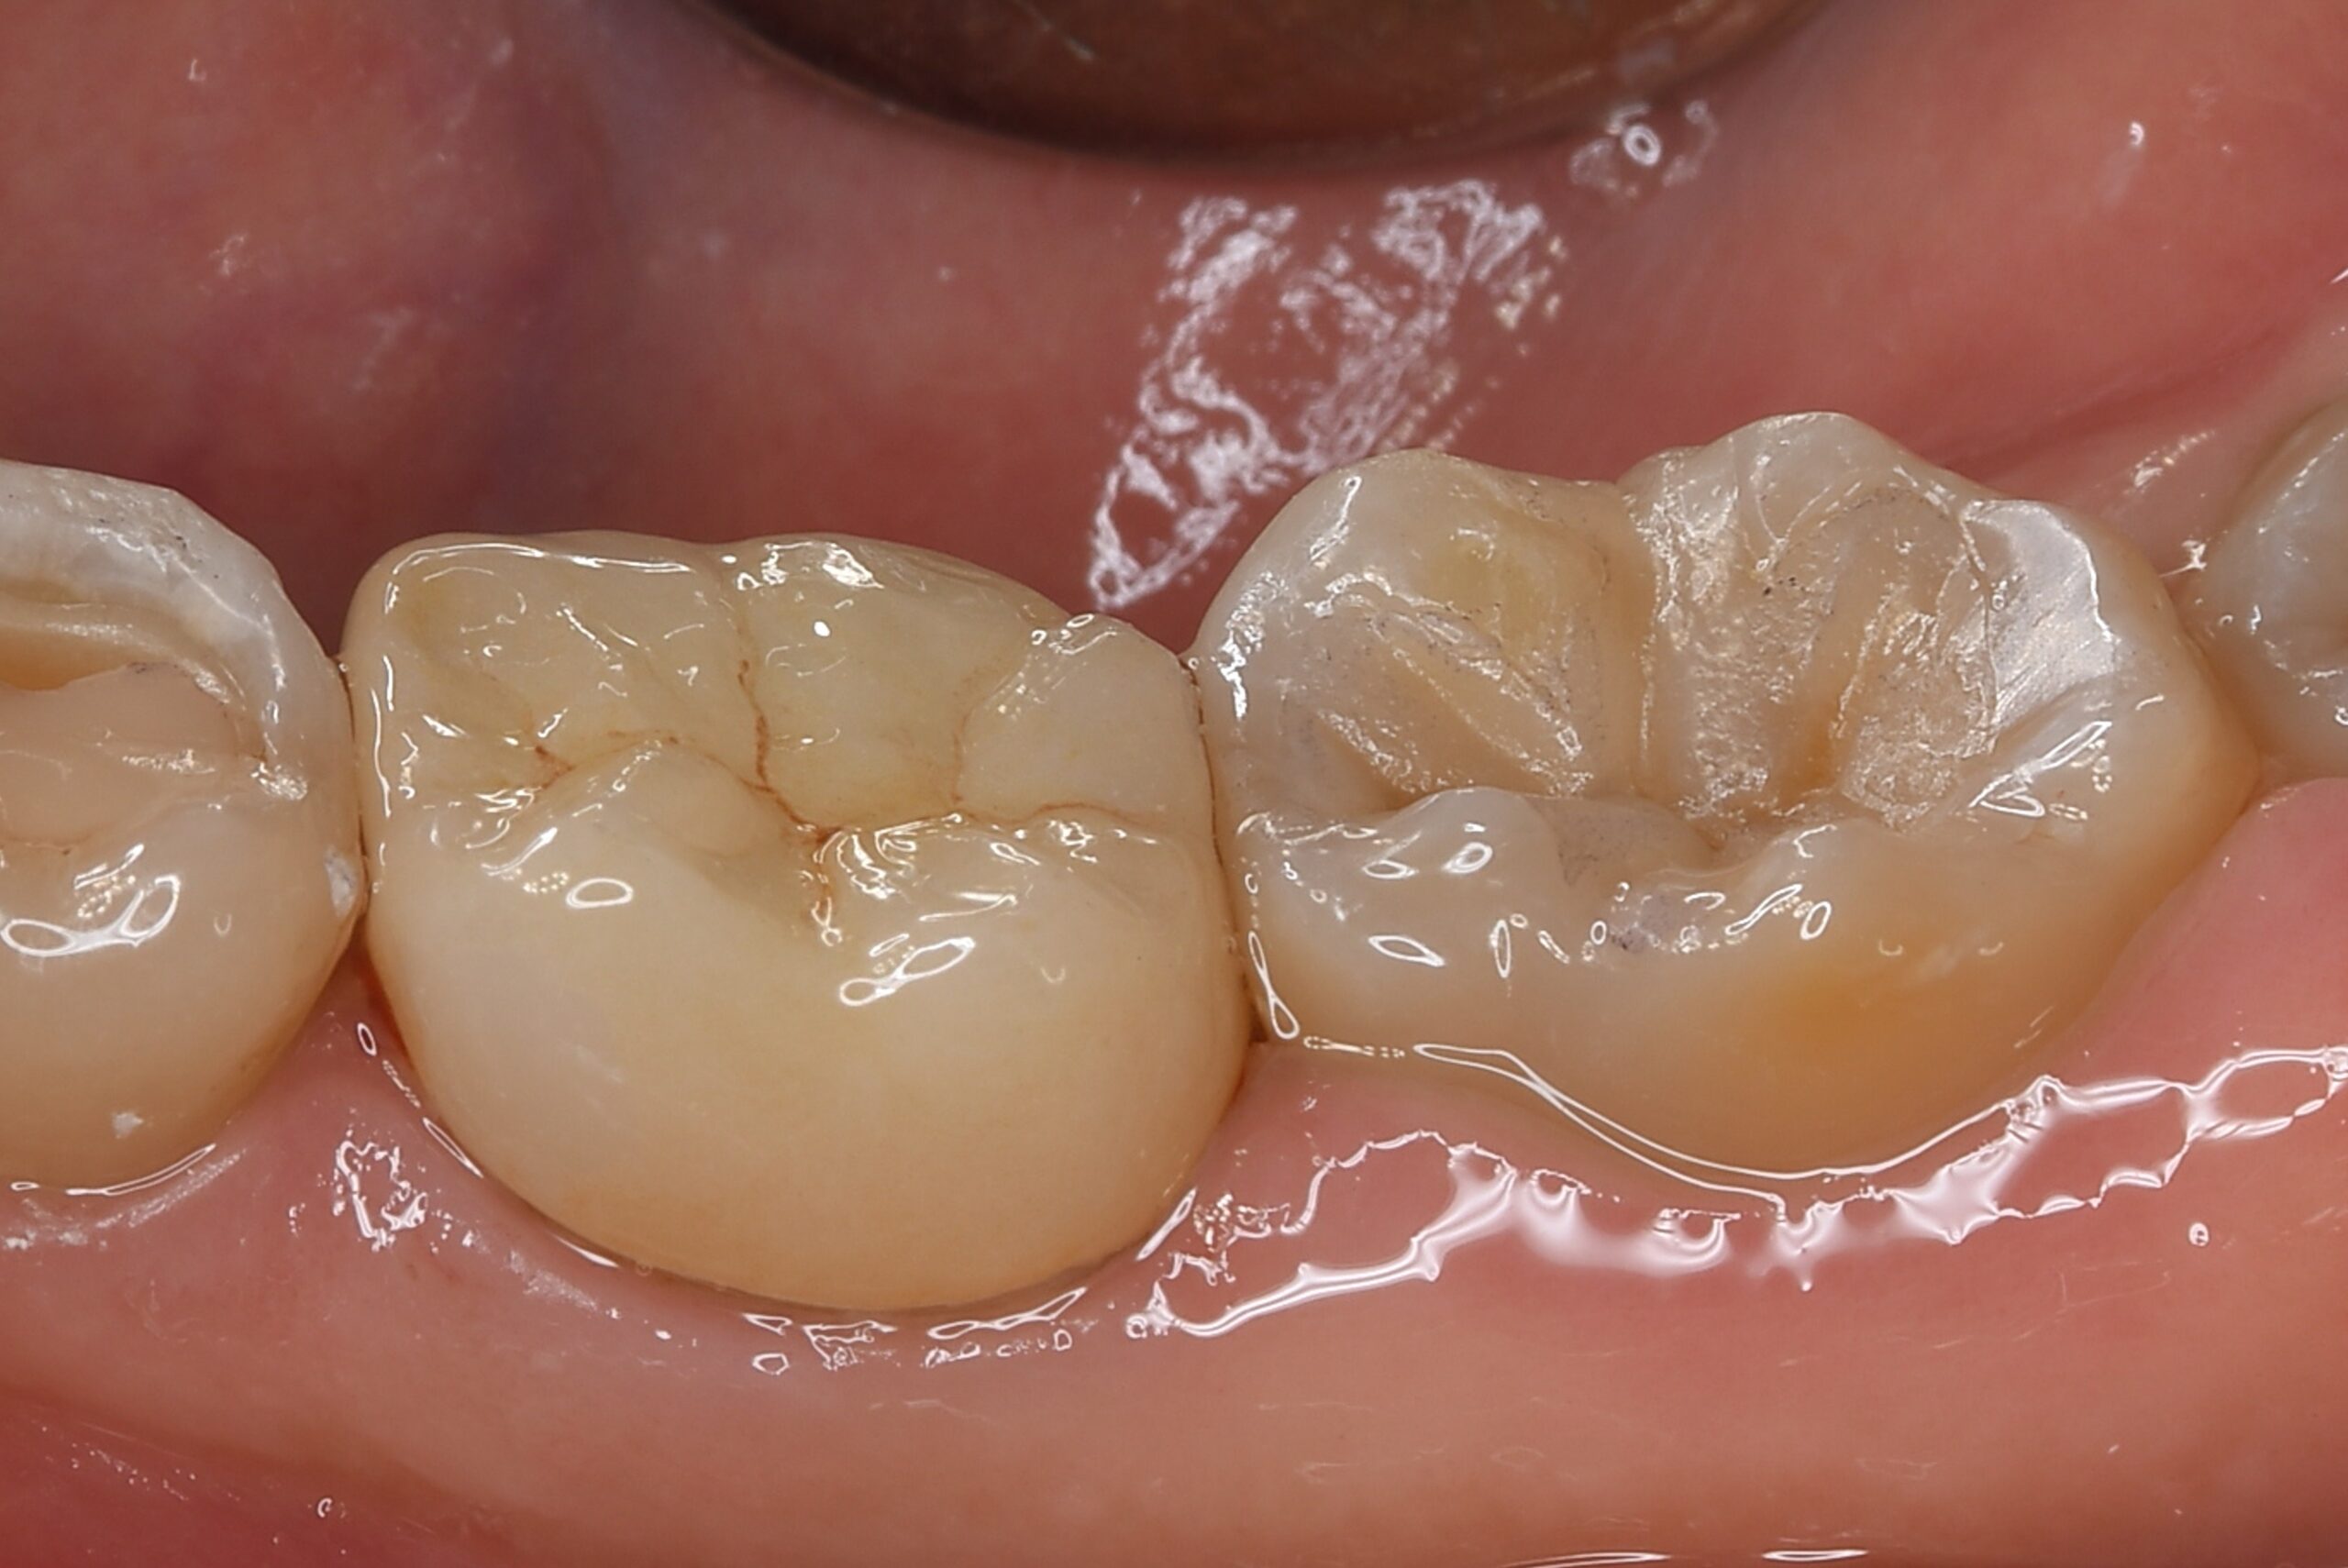

症例2

| 項目 | 詳細 |

|---|---|

| 患者様データ | 50代 女性 |

| 来院時の主訴 | 「左上の歯の周辺から膿が出て臭う。」 |

| 医院の診断 | 虫歯の再発、慢性根尖性歯周炎 |

| 通院期間 | 6ヶ月 |

| 来院回数 | 10回 |

| 治療費 | 580,000円(税抜) 《内訳》 精密感染根管治療80,000円(小臼歯)+100,000円(大臼歯)、ファイバーポストコア20,000円×2、セラミックブリッジ360,000円 |

| リスクと副作用 | ①根管治療歯は長期的には破折するリスク ②メインテナンスが必要 |

| ココがこだわりのポイント☝ |

ラバーダム防湿とマイクロスコープを使用して丁寧に治療を行いました。 再根管治療のため、殺菌性があり歯を補強することのできる根管充填材料を使用しています。 |